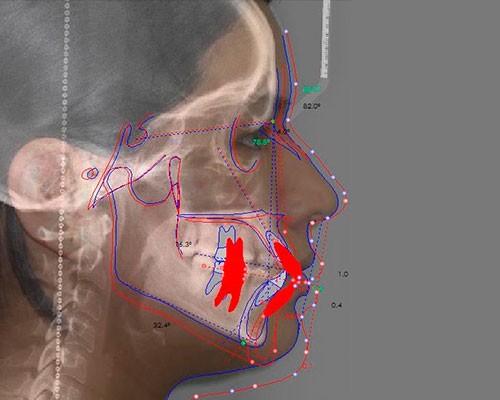

SISTEMAS DIGITALES 3D